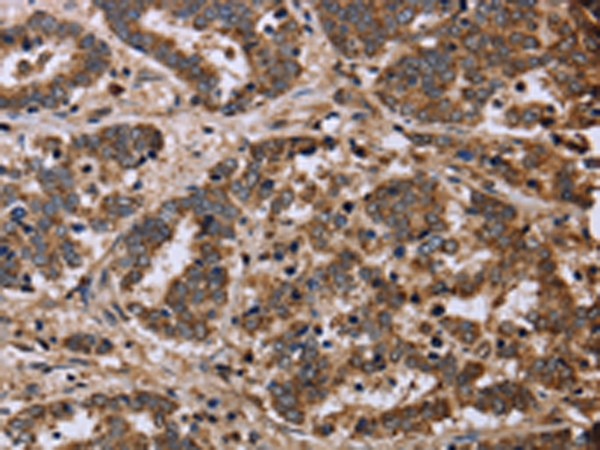

分类: 科研抗体货号: P08334别名: KYOT; SLIM; FHL-1; FHL1A; FHL1B; FLH1A; SLIM1; XMPMA; SLIM-1; SLIMMER应用: WB,IHC反应种属: Human, Mouse, Rat

分类: 科研抗体货号: P08332别名: T49; pT49应用: WB,IHC反应种属: Human, Mouse

分类: 科研抗体货号: P08330别名: WIT3.0; HSPC123-like应用: IHC反应种属: Human, Mouse, Rat

分类: 科研抗体货号: P08354别名: 87U6; ARCND1应用: IHC反应种属: Human, Mouse, Rat

分类: 科研抗体货号: P08329别名: FOP应用: WB,IHC反应种属: Human, Mouse

分类: 科研抗体货号: P08352别名: MYD118; GADD45BETA应用: IHC反应种属: Human, Mouse

分类: 科研抗体货号: P08328别名:应用: IHC反应种属: Human, Mouse

分类: 科研抗体货号: P08350别名:应用: WB,IHC反应种属: Human, Mouse, Rat

分类: 科研抗体货号: P08327别名: ZFGF5; FGF-18应用: WB,IHC反应种属: Human, Mouse, Rat

分类: 科研抗体货号: P08349别名: MCL; LRCC; HLRCC; MCUL1应用: WB,IHC反应种属: Human, Mouse, Rat